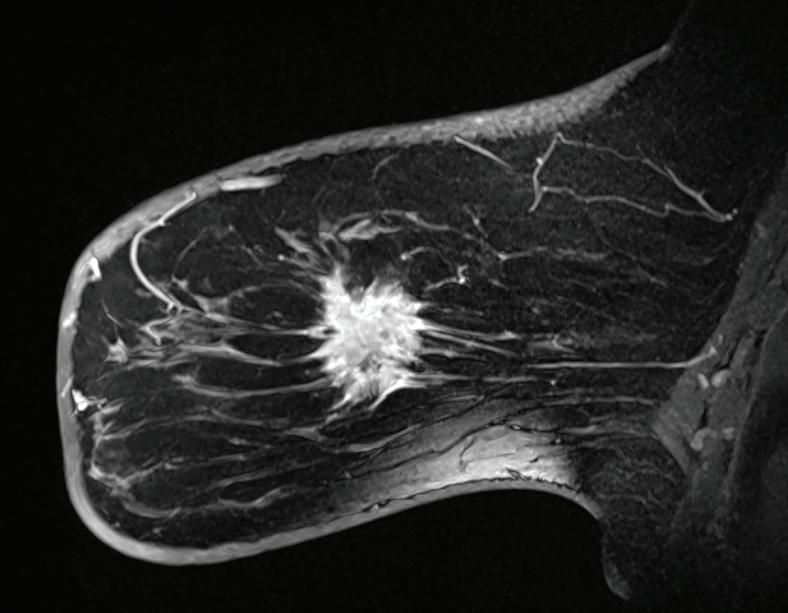

Your doctor says you should have a breast MRI and/or an MRI-guided breast biopsy. Both involve MRI, or magnetic resonance imaging, a technology that uses a magnetic field and pulses of radio wave energy to make detailed, high-quality images.

How are these procedures different and how can they help? Amanda Feibusch, MD, a radiologist at the Jacqueline M. Wilentz Comprehensive Breast Center at Monmouth Medical Center Southern Campus, explains.

What is a breast MRI?

A breast MRI is a test performed most commonly as a high-risk screening in addition to an annual mammogram. The breast MRI helps with problem-

solving following diagnostic imaging or with evaluating the extent of disease following a cancer diagnosis.

Intravenous contrast is required for a breast MRI. This entails administering a special dye that makes it easier for healthcare providers to see differences or abnormalities in the body. If an abnormality is detected on a breast MRI, the radiologist analyzing the images will recommend an MRIguided biopsy. This will determine if the abnormality is benign (noncancerous) or malignant (cancerous).

What is an MRI-guided breast biopsy?

An MRI-guided breast biopsy is a minimally invasive procedure performed to take a sample of the tissue in question. This sample can be used to evaluate a suspicious finding seen on a breast MRI and potentially diagnose cancer. The procedure usually takes about an hour.

What happens during the biopsy?

We take a series of images, and the radiologist locates the area in question. We inject a local anesthetic for comfort, make a very small nick in the skin and take a few samples of tissue. The actual tissue sampling only takes a few minutes. Tissue samples are sent to the pathology lab for analysis. A tiny marker is then placed in the sampled area to provide a reference point if surgical intervention is required following the tissue diagnosis, which is obtained within a couple of days.

What’s the biggest benefit?

Early detection saves lives. MRIguided breast biopsy provides a minimally invasive way to sample suspicious tissue in the breast. It allows pathologic diagnosis that will provide important information for a surgeon if surgical management is subsequently recommended.